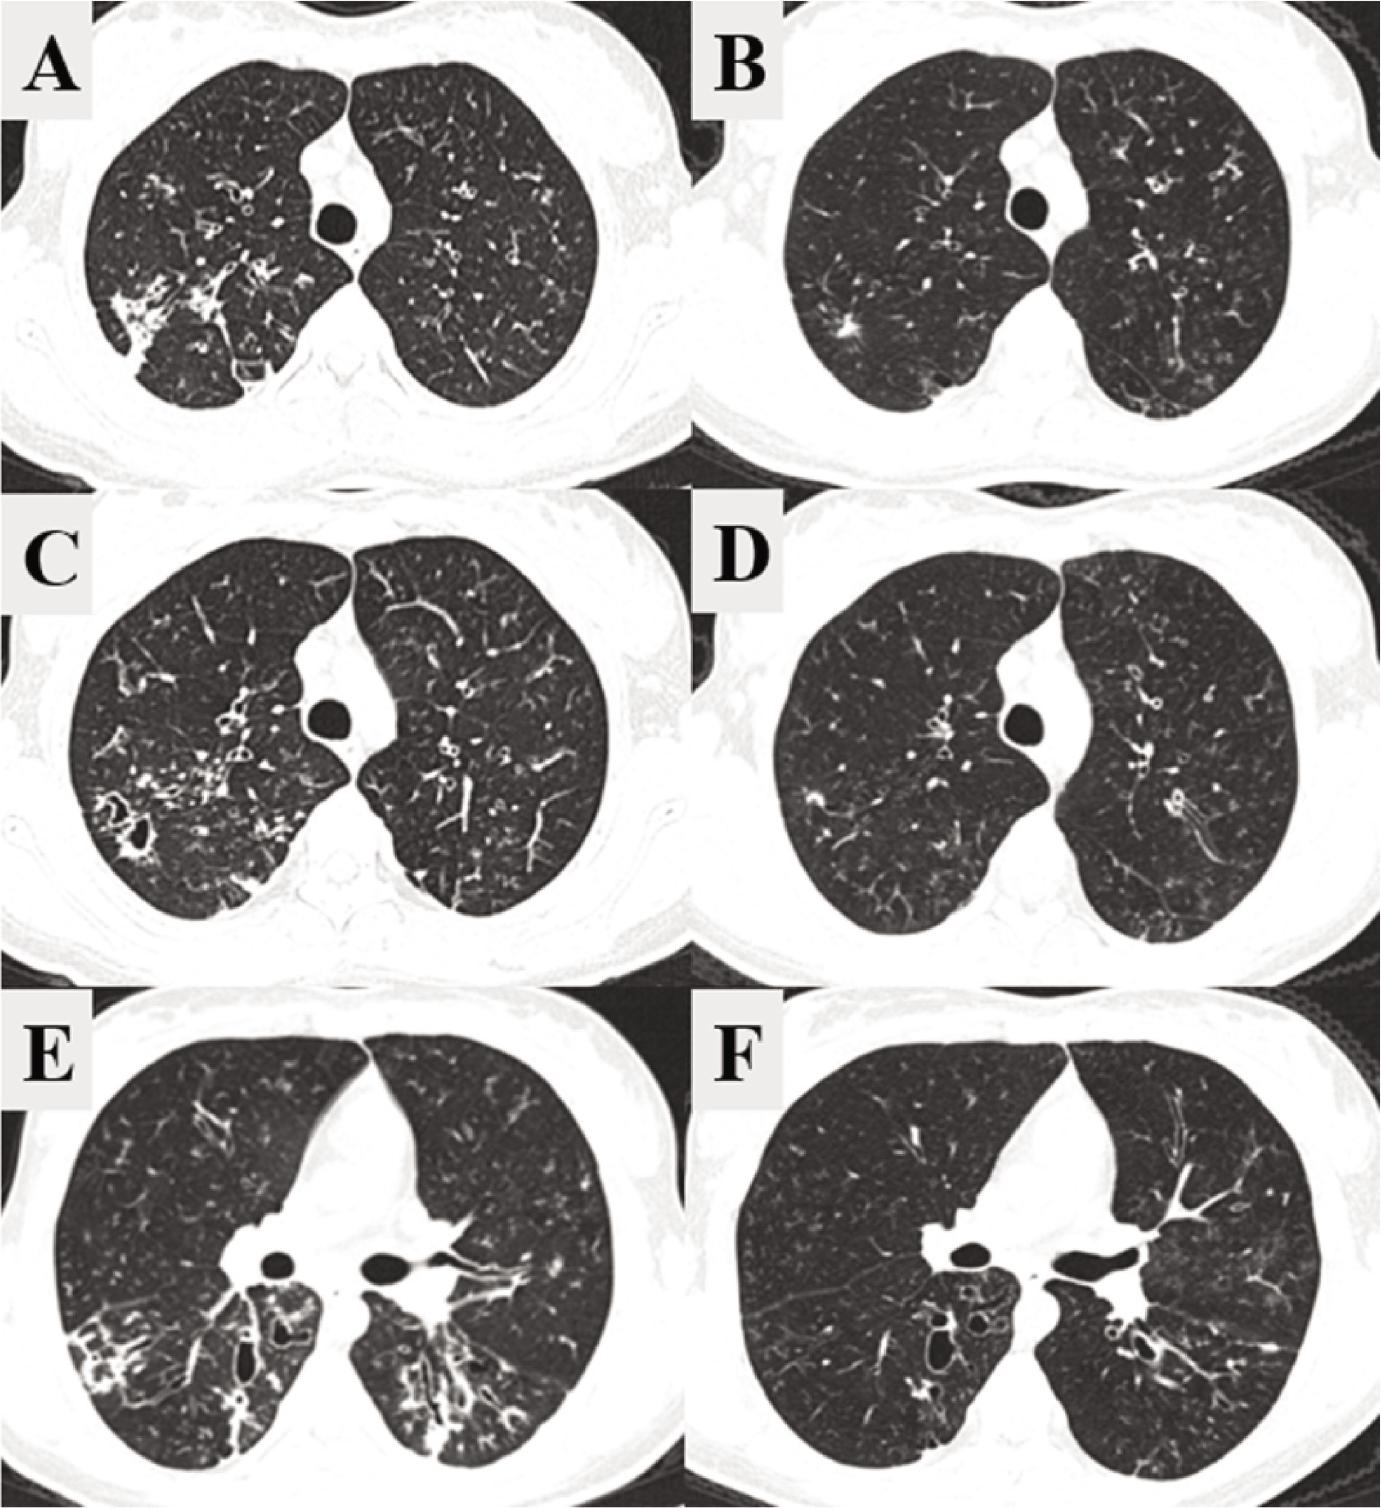

Figure 1.

Figure 2.

Statistically significant changes in group mean values of ppFEV1, sweat chloride test, and Bhalla score_

| Total Bhalla score | 14.55 | 18.27 | 3.73 | (2.8511, 4.6035) | < 0.001 |

Comparison of mean values of CT parameters assessed before and after therapeutic intervention_

| Bronchiectasis | 1.73 | 1.36 | –0.36 | (–0.6479, –0.0794) | 0.125 |

| Wall thickening | 1.09 | 0.18 | –0.91 | (–1.3039, –0.5143) | 0.008 |

| Mucus plugging | 1.64 | 0.55 | –1.09 | (–1.3948, –0.7877) | 0.002 |